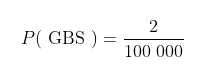

条件概率的第一个例子将研究流感疫苗和接种疫苗可能出现的并发症。当在美国接种流感疫苗时,你通常会收到知情同意书。它告诉你与之相关的各种风险,其中之一是吉兰它巴雷综合征(Guillain-Barré syndrome,GBS)的发病率会增加。GBS是一种非常罕见的疾病,它会造成人体的免疫系统攻击神经系统,从而导致潜在的、危及生命的并发症。根据美国疾病控制与预防中心的数据,在某个特定年份,人们患上GBS的概率为2/100 000。这个概率可以表示为: